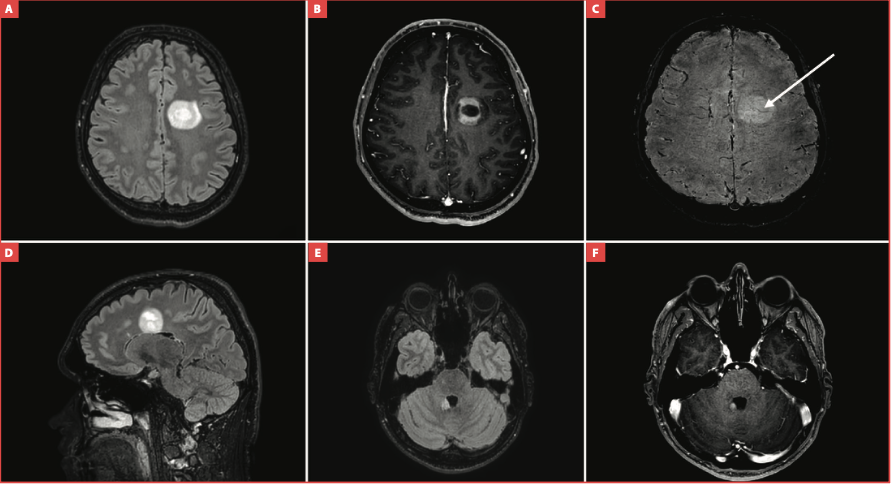

Un jeune patient caucasien de 20 ans

est adressé aux urgences pour un épisode

aigu d’aphasie non fluente d’une durée de

trente minutes, associé à des troubles de

la marche et des vertiges, spontanément

résolutifs à l’exception des troubles de la

marche.

L’anamnèse retrouve une irritabilité,

de légers troubles du comportement et des

troubles visuo-spatiaux modérés apparus

il y a deux mois. Il rapporte également des

troubles phasiques et des nausées depuis

deux semaines. Un scanner sans injection

puis avec analyse des troncs supra- aortiques

au temps artériel est réalisé aux urgences et

ne montre aucune anomalie.

Le patient est

renvoyé à son domicile avec une ordonnance

pour réaliser une IRM cérébrale en externe.

L’IRM donne les images ci-dessous (fig. 1). Le patient vous est adressé pour suspicion de néoplasie cérébrale.

Fig. 1 : IRM cérébrale du patient. Coupe axiale en séquence FLAIR (fluid attenuated inversion-recovery) (panel A), coupe axiale en séquence T1 après injection de gadolinium (panel B), coupe axiale en séquence de susceptibilité magnétique (panel C), coupe sagittale en séquence FLAIR (panel D), coupe axiale en séquence FLAIR (panel E), coupe axiale en séquence T1 après injection de gadolinium (panel F).